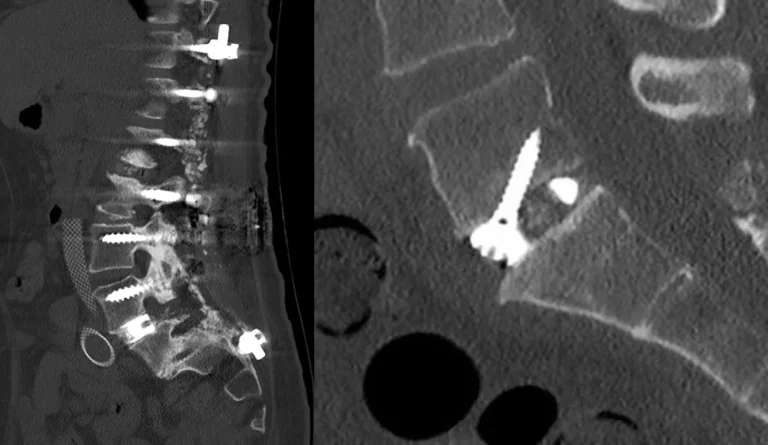

CT scan showing spinal instrumentation with screws and rods in place.

ALIF: Highest Complication Rate